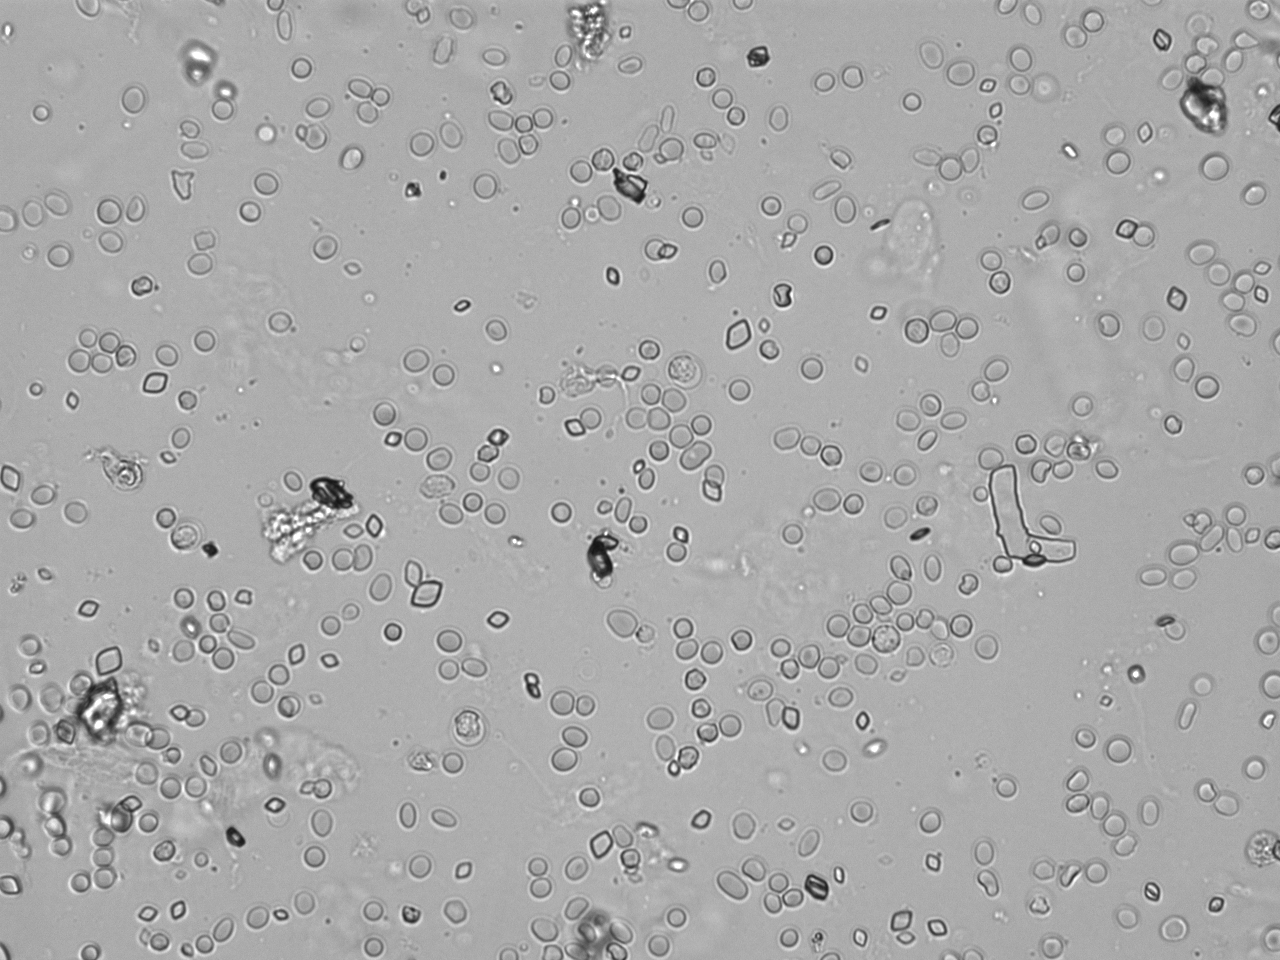

Urin-Feature: Harnskristalle_Rhomboid